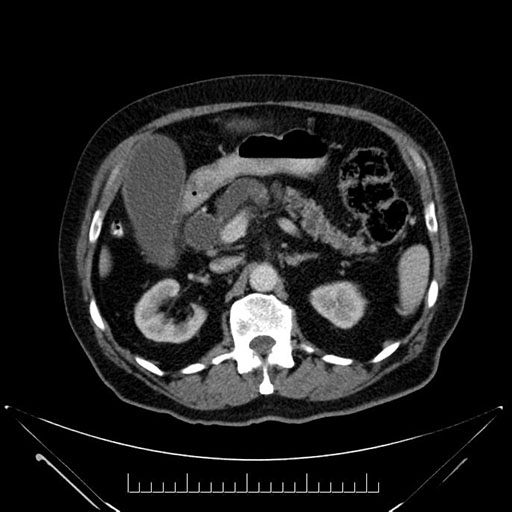

Axial - stented